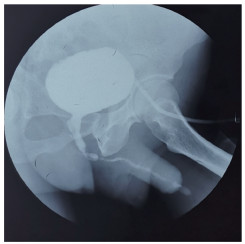

1.2 术前评估局部尿道查体观察尿道外口、阴茎头、包皮外形及阴茎段尿道海绵体是否可触及质硬瘢痕组织,见图 1。顺行或逆行尿道造影检查观察前尿道狭窄的部位和长度,如尿道外口狭窄不能行逆行造影,则仅行顺行造影,见图 2。术前均于门诊行耻骨上膀胱穿刺造瘘术。

| 图 2 术前顺行尿道造影 Fig.2 Preoperative voiding cystourethrogram |

2 结果共随访10~67个月,平均(34.4±18.1)个月。术后1个月评估,排尿通畅31例(91.2%);尿流率检查最大尿流率为12.0~30.5 mL/s,平均(19.7±5.3)mL/s,较术前入院时尿流率有统计学差异(P < 0.01)。尿道狭窄再发者3例(8.8%),1例术后6个月尿道外口狭窄再次行尿道外口成形术;2例吻合口狭窄,分别发生于术后12个月及术后26个月,行尿道扩张1例,再次行颊黏膜替代1例。移植黏膜均存活,见图 8。尿道造影可见成形尿道宽阔,见图 9,无尿道皮肤瘘及感染并发症。本研究中,术中取供体舌黏膜26例,舌黏膜+颊黏膜5例,舌黏膜+唇黏膜3例,患者对口腔黏膜取材耐受良好,供体区创面术后观察5~7 d愈合良好,取下唇黏膜者术后无唇内翻发生,术后4例有口腔紧缩感及麻木感,于术后2~3个月恢复。

| 图 9 术后2个月尿道造影 Fig.9 Postoperative voiding cystourethrogram two months later |